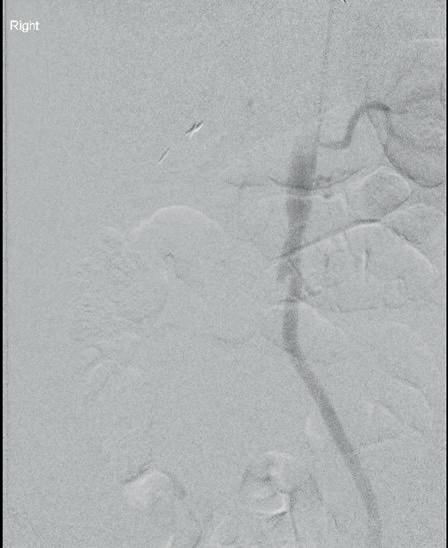

Left: Pre- and postoperative images (courtesy of Dittmar Böckler) of the first European implantation of the Gore Tag TBE; above: Dittmar Böckler performing the implantation